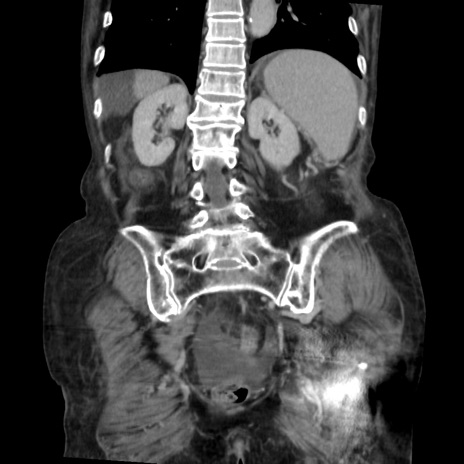

【症例】80歳代 女性

【主訴】腹部膨満感

【現病歴】他院にて肝硬変にてフォロー中。1週間前から便秘、腹部膨満感、臍部腫瘤あり受診となる。

【既往歴】肝硬変

【身体所見】腹部膨隆あり、皮膚変化なし、疼痛なし。

【データ】WBC 4600、CRP 0.25